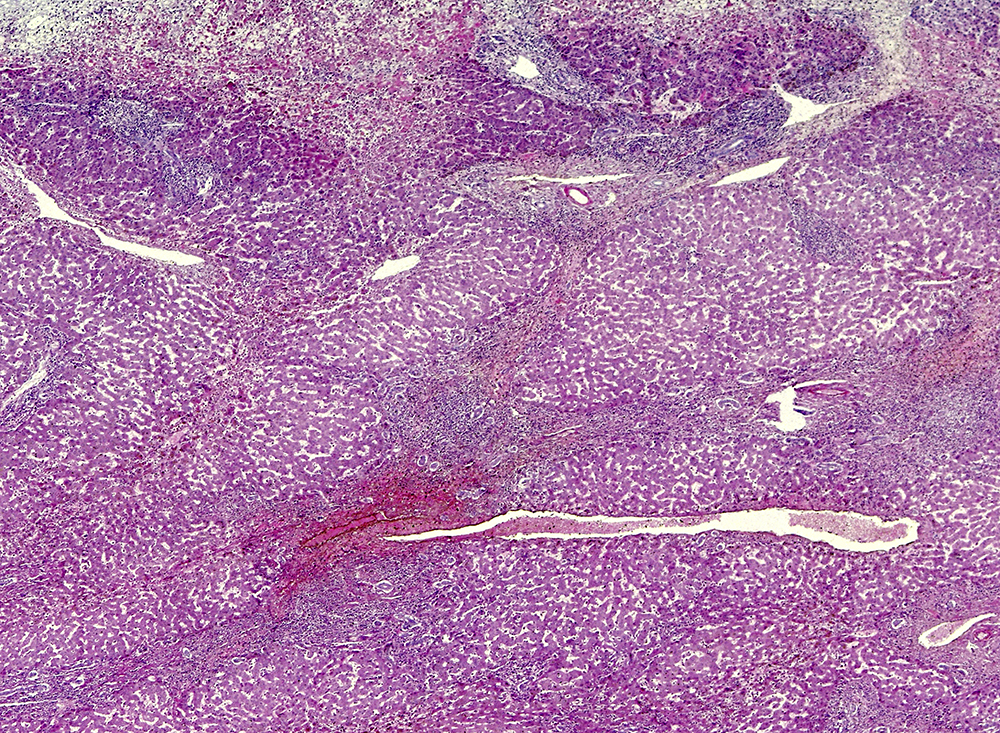

Leverbiopsi er nødvendig for å stille diagnosen og skal tas før behandling, da behandlingen kan kamuflere histologiske funn og vanskeliggjøre diagnostikken. Typiske histologiske funn ved sykdommen er inflammatorisk aktivitet i portalområdene som sprer seg innover i leverlobuli (interfasehepatitt) og gir økt mengde plasmaceller (1). De histologiske funnene er imidlertid ikke spesifikke for autoimmun hepatitt, og diagnosen baserer seg også på forhøyet serum-immunglobulin G (IgG) og/eller moderat eller høyt titer av visse autoantistoffer (kjerneantistoffer (ANA), glatt muskulatur-antistoffer (SMA)/anti-f-actin, eventuelt anti-LKM (lever-nyre-mikrosom)-1 og anti-SLA (anti-løselige leverantigen)) (1). Anti-SLA kan iblant være det eneste positive autoantistoffet. Dette bør tas dersom de andre autoantistoffene er negative eller inkonklusive. Virale hepatitter skal utelukkes. Kroniske leversykdommer som kan representere differensialdiagnoser og/eller komorbiditet (f.eks. ikke-alkoholisk fettleversykdom, som ses hos ca. ¼, eller annen autoimmun leversykdom) bør identifiseres.